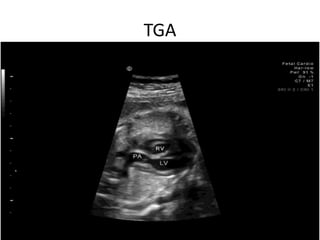

This echocardiogram report describes various views of the heart including the short axis, long axis, and four chamber views. It notes findings such as a right aortic arch, right pulmonary artery with thrombus, and transposition of the great arteries. The report also discusses acoustic windows, the aortic arch, ductus arteriosus, and mitral Doppler imaging.